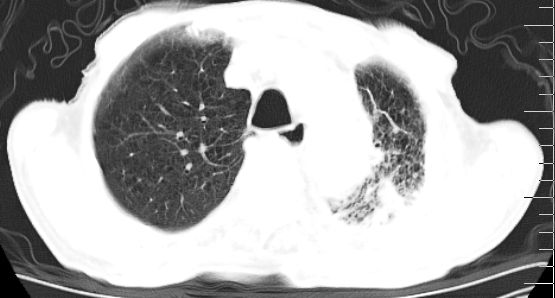

标题: CT10141:男、84岁,咳嗽、咯血1年。 [打印本页]

标题: CT10141:男、84岁,咳嗽、咯血1年。

支持左侧中央型肺癌伴下叶肺不张\\纵隔淋巴结转移.左侧包裹性胸腔积液\\心包积液.左侧少量胸腔积液..慢性支气管炎伴部分间质纤维化.

咯血病史较长,左肺下叶实变,体积未明显缩小,隐约可见血管影及坏死阴影,双肺门及纵隔淋巴结增大,心包增厚积液,纵隔右移位,单侧胸腔积液,首先考虑:大叶型肺泡癌伴纵隔心包转移。